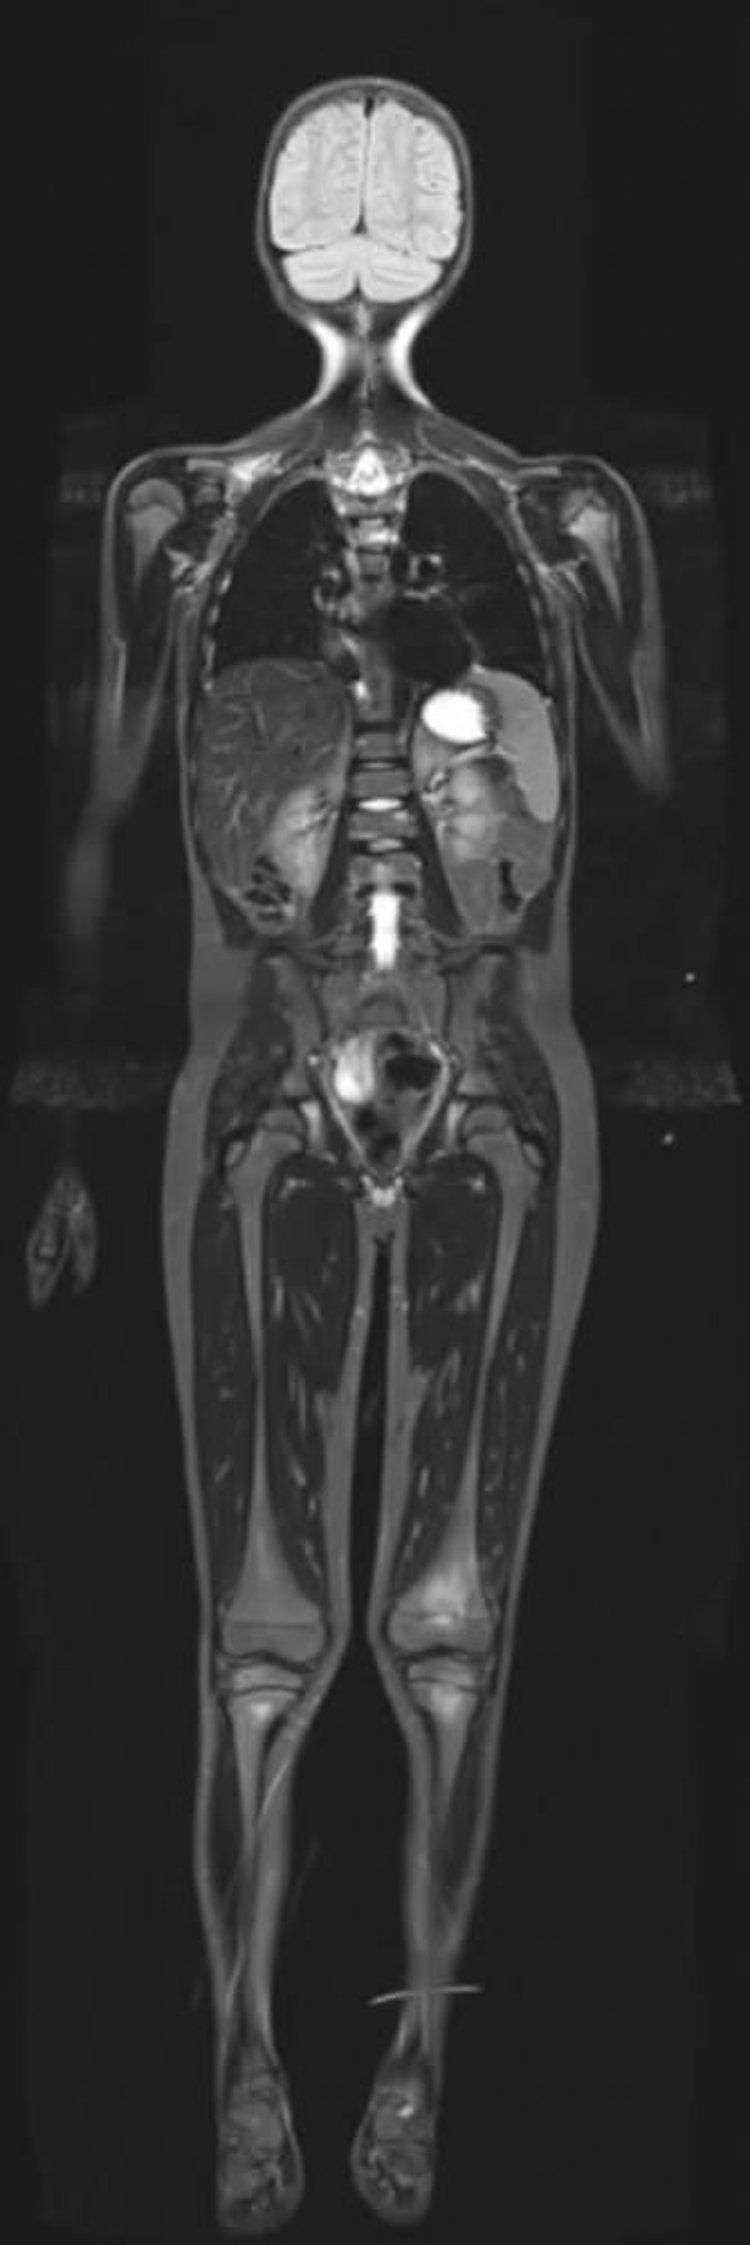

IRM de récupération d’inversion courte en T1 (STIR, Short T1 Inversion Recovery MRI)

L'IRM de récupération d’inversion courte T1 (STIR, Short T1 Inversion Recovery MRI) peut supprimer les signaux du tissu adipeux, ce qui permet l'augmentation du contraste d'autres tissus riches en eau.

Image courtoisie de Hakan Ilaslan, MD.